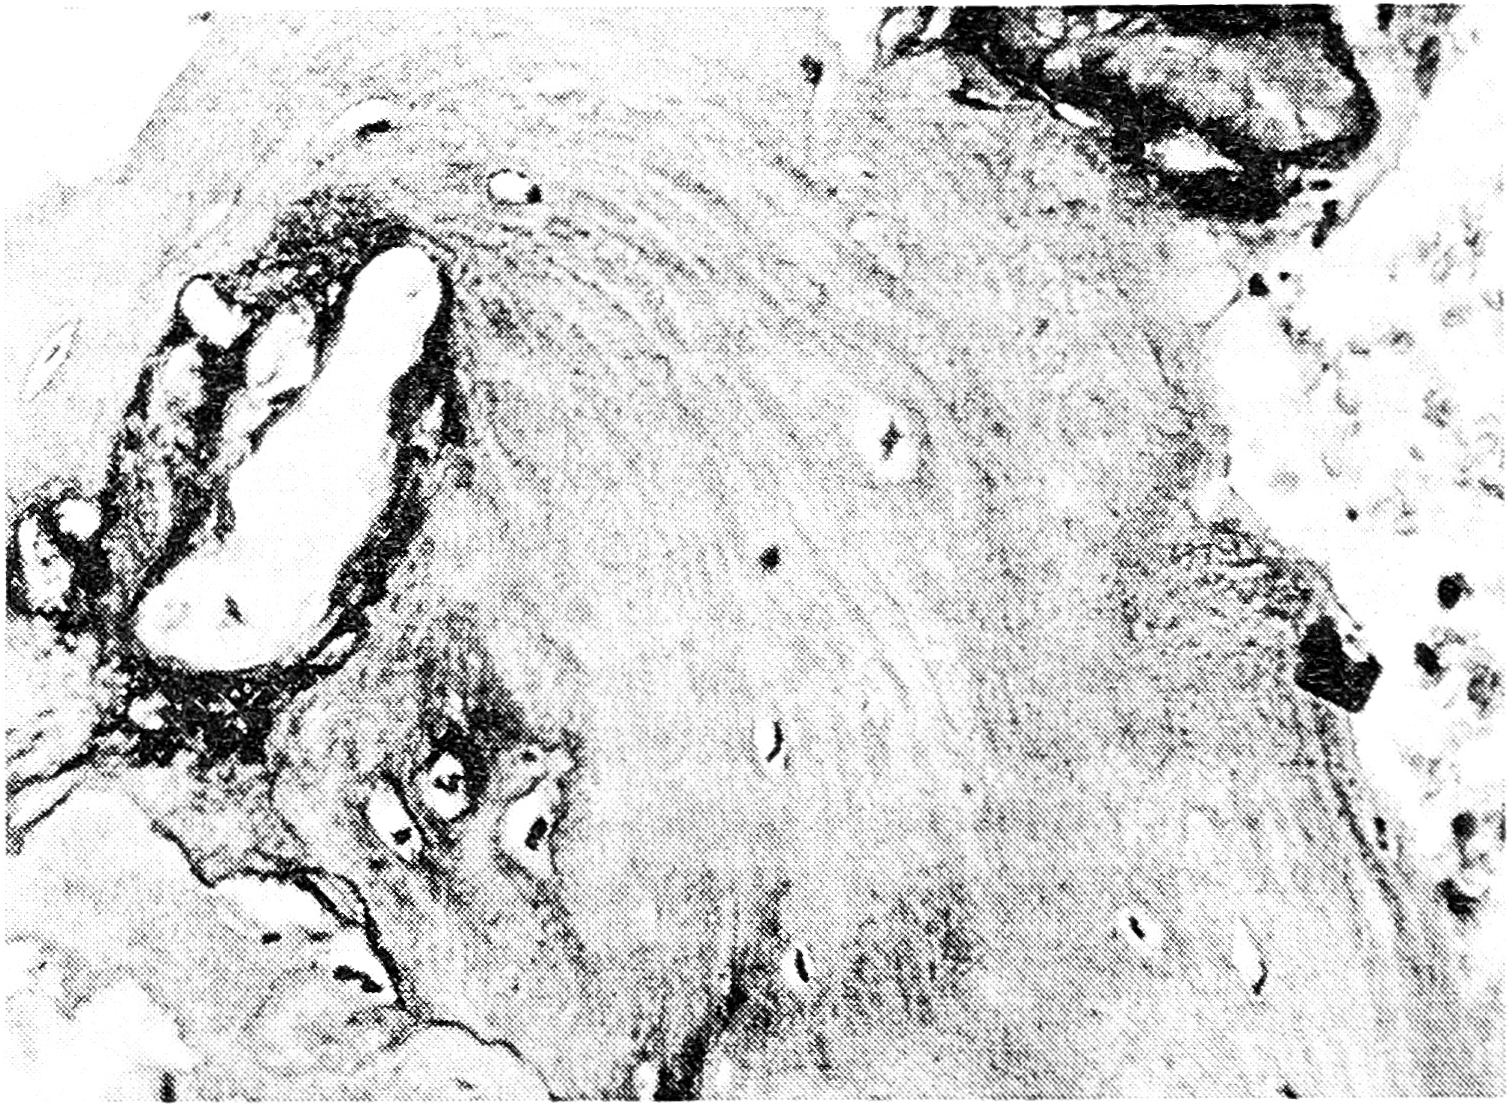

Гистологическое исследование операционного материала показало, что к 4-му месяцу после имплантации коллапана в костном дефекте, образовавшемся при секвестрнекрэктомии, происходят активные процессы остеогенеза. Определяются новообразованные костные балки, содержащие включения остатков гидроксиапатита (рис. 1), являющегося основой коллапана. В участках, расположенных ближе к центру дефекта, балки имеют в основном остеоидный характер, тогда как в краевых участках костные трабекулы более зрелые, постепенно приобретающие пластинчатое строение. Признаков воспалительного процесса в межбалочных пространствах не наблюдается. Частицы коллапана в виде гидроксиапатита в основном обнаруживаются внутрикостно, в межтрабекулярных пространствах они встречаются редко, при этом клеточной реакции вокруг них не определяется.

Рис. 1. Формирование костных трабекул, содержащих включения гидроксиапатита. Срок после операции 4 мес.

Окраска гематоксилином и эозином. Ув. 125.